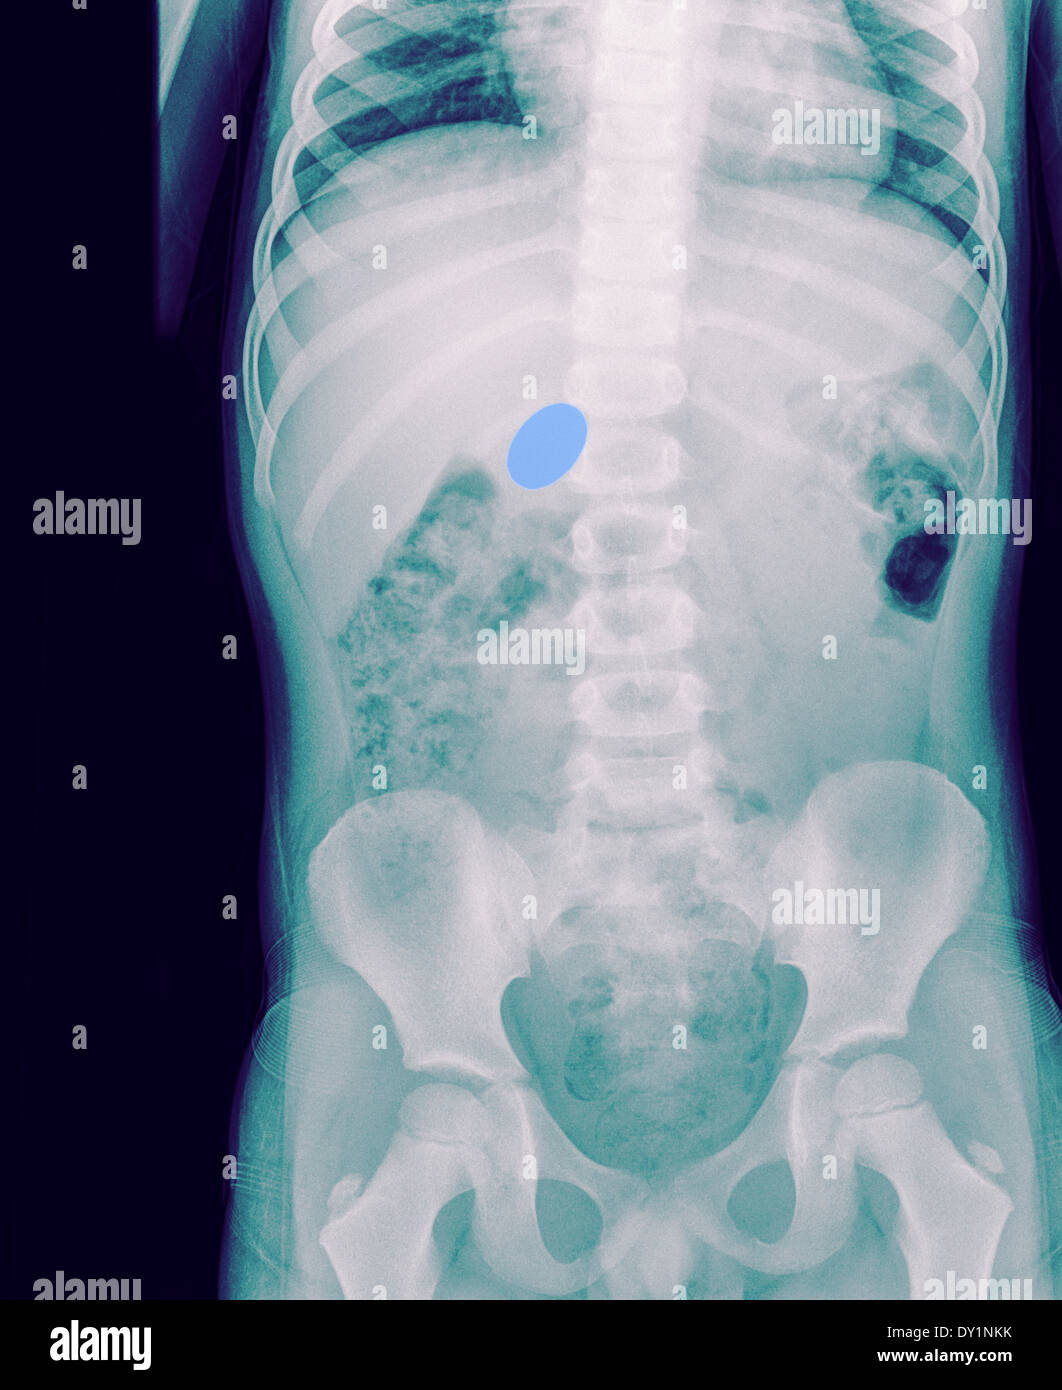

Shotgun pellets Radiology at St. Vincent's University Hospital Child Swallowed Lead Pellet the identification of a neonate, infant, or child who has been exposed to lead must be viewed as a public health. one area of concern is the ingestion of items containing lead, due to the uncorrectable effects of lead exposure. this article presents 3 cases of children ingesting lead ammunition, all receiving gastrointestinal (gi) decontamination and. Even. Child Swallowed Lead Pellet.

Child Swallowed Lead Pellet . Even low levels of lead in blood have been shown to negatively. one area of concern is the ingestion of items containing lead, due to the uncorrectable effects of lead exposure. the identification of a neonate, infant, or child who has been exposed to lead must be viewed as a public health. this article presents 3 cases of children ingesting lead ammunition, all receiving gastrointestinal (gi) decontamination and. infants and children are at higher risk than adults for lead exposure due to their smaller size and proportionately larger dose of. this article presents 3 cases of children ingesting lead ammunition, all receiving gastrointestinal (gi) decontamination and. protecting children from exposure to lead is important to lifelong good health.

this article presents 3 cases of children ingesting lead ammunition, all receiving gastrointestinal (gi) decontamination and. protecting children from exposure to lead is important to lifelong good health. infants and children are at higher risk than adults for lead exposure due to their smaller size and proportionately larger dose of. one area of concern is the ingestion of items containing lead, due to the uncorrectable effects of lead exposure. the identification of a neonate, infant, or child who has been exposed to lead must be viewed as a public health. Even low levels of lead in blood have been shown to negatively. this article presents 3 cases of children ingesting lead ammunition, all receiving gastrointestinal (gi) decontamination and.